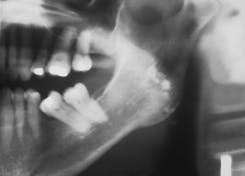

Case 2

Condensing Osteitis

1. Identify the most common location for condensing osteitis.

2. Identify the radiographic appearance of condensing osteitis.

3. Identify the treatment of choice for condensing osteitis.

4. Identify the true statement concerning condensing osteitis.